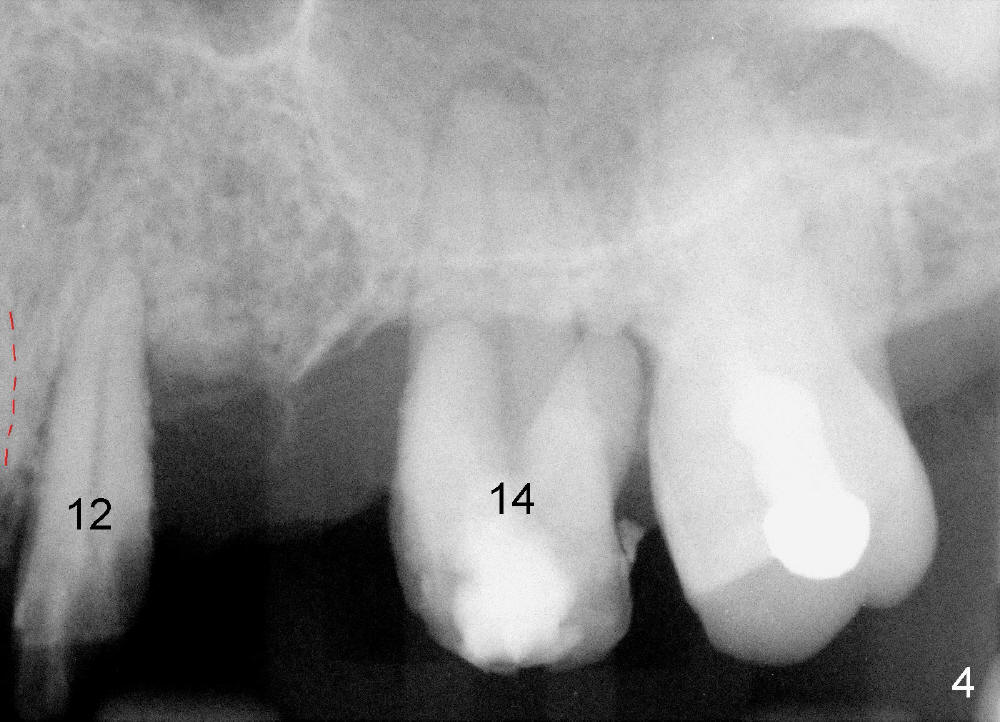

A 53-year-old lady has a failing bridge (Fig.1). There is severe bone loss around the buccal roots of #14 (*). Purulent discharge is from the gingival sulcus (Fig.2 <) with localized gingival erythema and edema (*). When the bridge is removed, the tooth #12 is found nonsalvageable (Fig.3,4). These two teeth are to be replaced by immediate implants (Fig.5). Although the sinus floor is low buccally (arrowheads), a 6x14 mm gingiva-level implant can be placed in the septum close to the palatal socket or in the palatal socket at the site of #14.

Placement of immediate implant at the site of #12 is relatively easy. Adjustment is more or less mesiodistal. A 2 mm pilot drill (Fig.6 P) is found close to the root of the tooth #11 (red dashed line). The osteotomy is then moved distally (Fig.6 arrow). When 4.5x20 mm tap (Fig.7: #12) and 4.5x17 mm implant (Fig.8 I) are placed, there is distance from the root of the neighboring tooth. Insertion torque of the both implants is >60 Ncm. Abutments are placed (A in Fig.8) for immediate provisional.